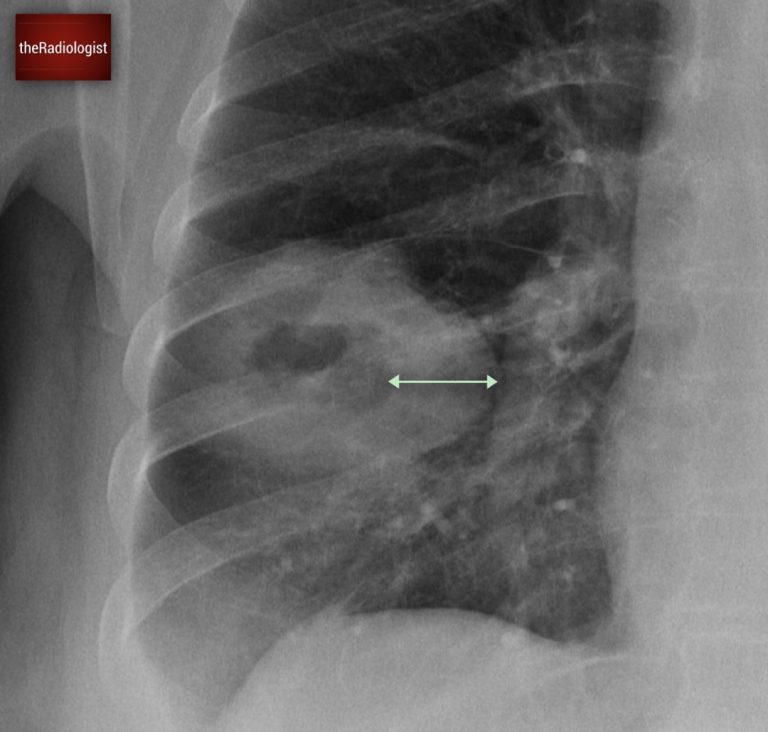

To solidify the diagnosis and to stage the patient, a CT scan was performed. As well as the cavitating lesion within the lung, it revealed a large mass invading the chest wall, clearly eroding the ninth rib. This finding strongly supported the suspicion of malignancy.

An ultrasound-guided biopsy of the chest wall mass was then carried out, confirming the presence of lung cancer with a large chest wall metastasis.

There is a soft tissue mass within the right chest wall destroying the ninth rib.